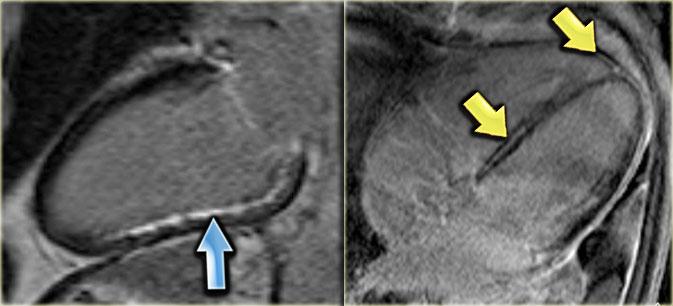

Trái: hiện tượng không tái tưới máu, Phải: bốn tháng sau có ngấm thuốc xuyên thành cho thấy nhồi máu xuyên thành

Hiện tượng không tái tưới máu (No-reflow)

Hiện tượng không tái tưới máu là tình trạng máu không thể tưới lại vùng thiếu máu sau khi tắc nghẽn cơ học đã được giải phóng hoặc bắc cầu.

Các vùng không tái tưới máu được xác định trên ảnh ngấm thuốc muộn dưới dạng vùng lõi giảm tín hiệu được bao quanh bởi viền ngấm thuốc.

Hình ảnh này cho thấy sự hiện diện của tổn thương vi mạch tại vùng lõi của ổ nhồi máu.

Sự hiện diện của vùng ‘không tái tưới máu’ có liên quan đến tiên lượng chức năng xấu hơn, diện tích nhồi máu lớn hơn và kết cục lâm sàng bất lợi [8,9].

Cả nhồi máu cấp tính và mạn tính đều biểu hiện ngấm thuốc muộn, tuy nhiên nhồi máu cấp tính thường có thể được phân biệt bởi sự hiện diện của vùng ‘không tái tưới máu’ và tăng tín hiệu trên ảnh chuỗi xung T2W.